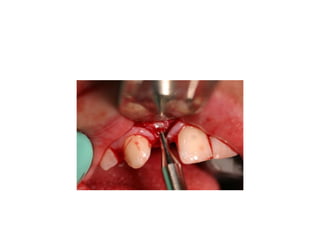

pre-op

implants are placed w/in restorative

Management of missing upp incisor